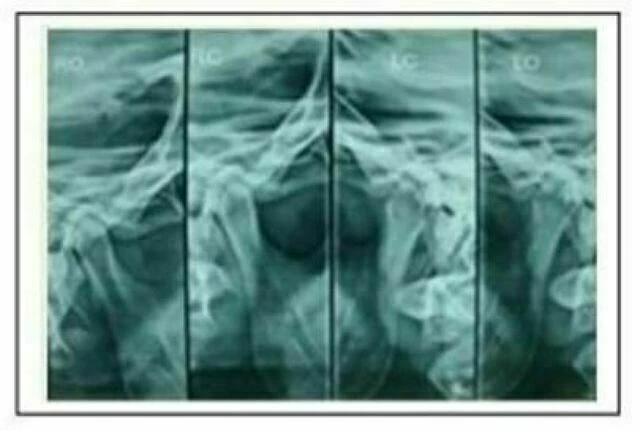

d. Tomogram: Cho các trường hợp có dấu hiệu bất thường về khớp thái dương hàm rõ rệt, cần phải có thêm phim này trong bệnh án.

e. Phim cổ tay: sử dụng để xác đinh tăng trưởng đang còn ở bệnh nhân. Phim này là tiêu chuẩn củaMỌI trường hợp bệnh nhân hạng III đang còn tăng trưởng